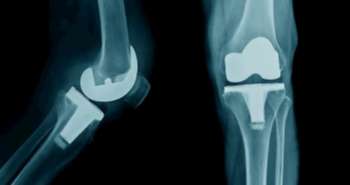

Several systematic reviews or meta-analyses concerning platelet-rich plasma (PRP) in treating knee osteoarthritis (OA) have been published. But definite conclusions about using PRP treating knee OA cannot yet be made with absolute confidence. Therefore in the present study, Xing D et al demonstrates that PRP is an effective intervention in treating knee OA without increased risk of adverse events.

The present overview illustrates that PRP is an efficient approach in managing knee OA without enhanced risk of side effects. Consequently, the current findings may help decision-makers understand and select PRP with more reliance.